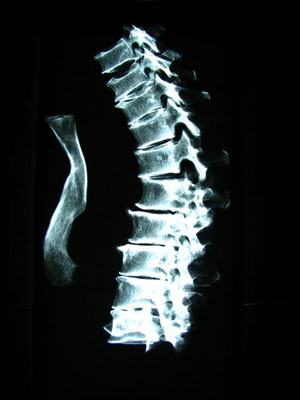

Römischer Patient auf dem Untersuchungstisch